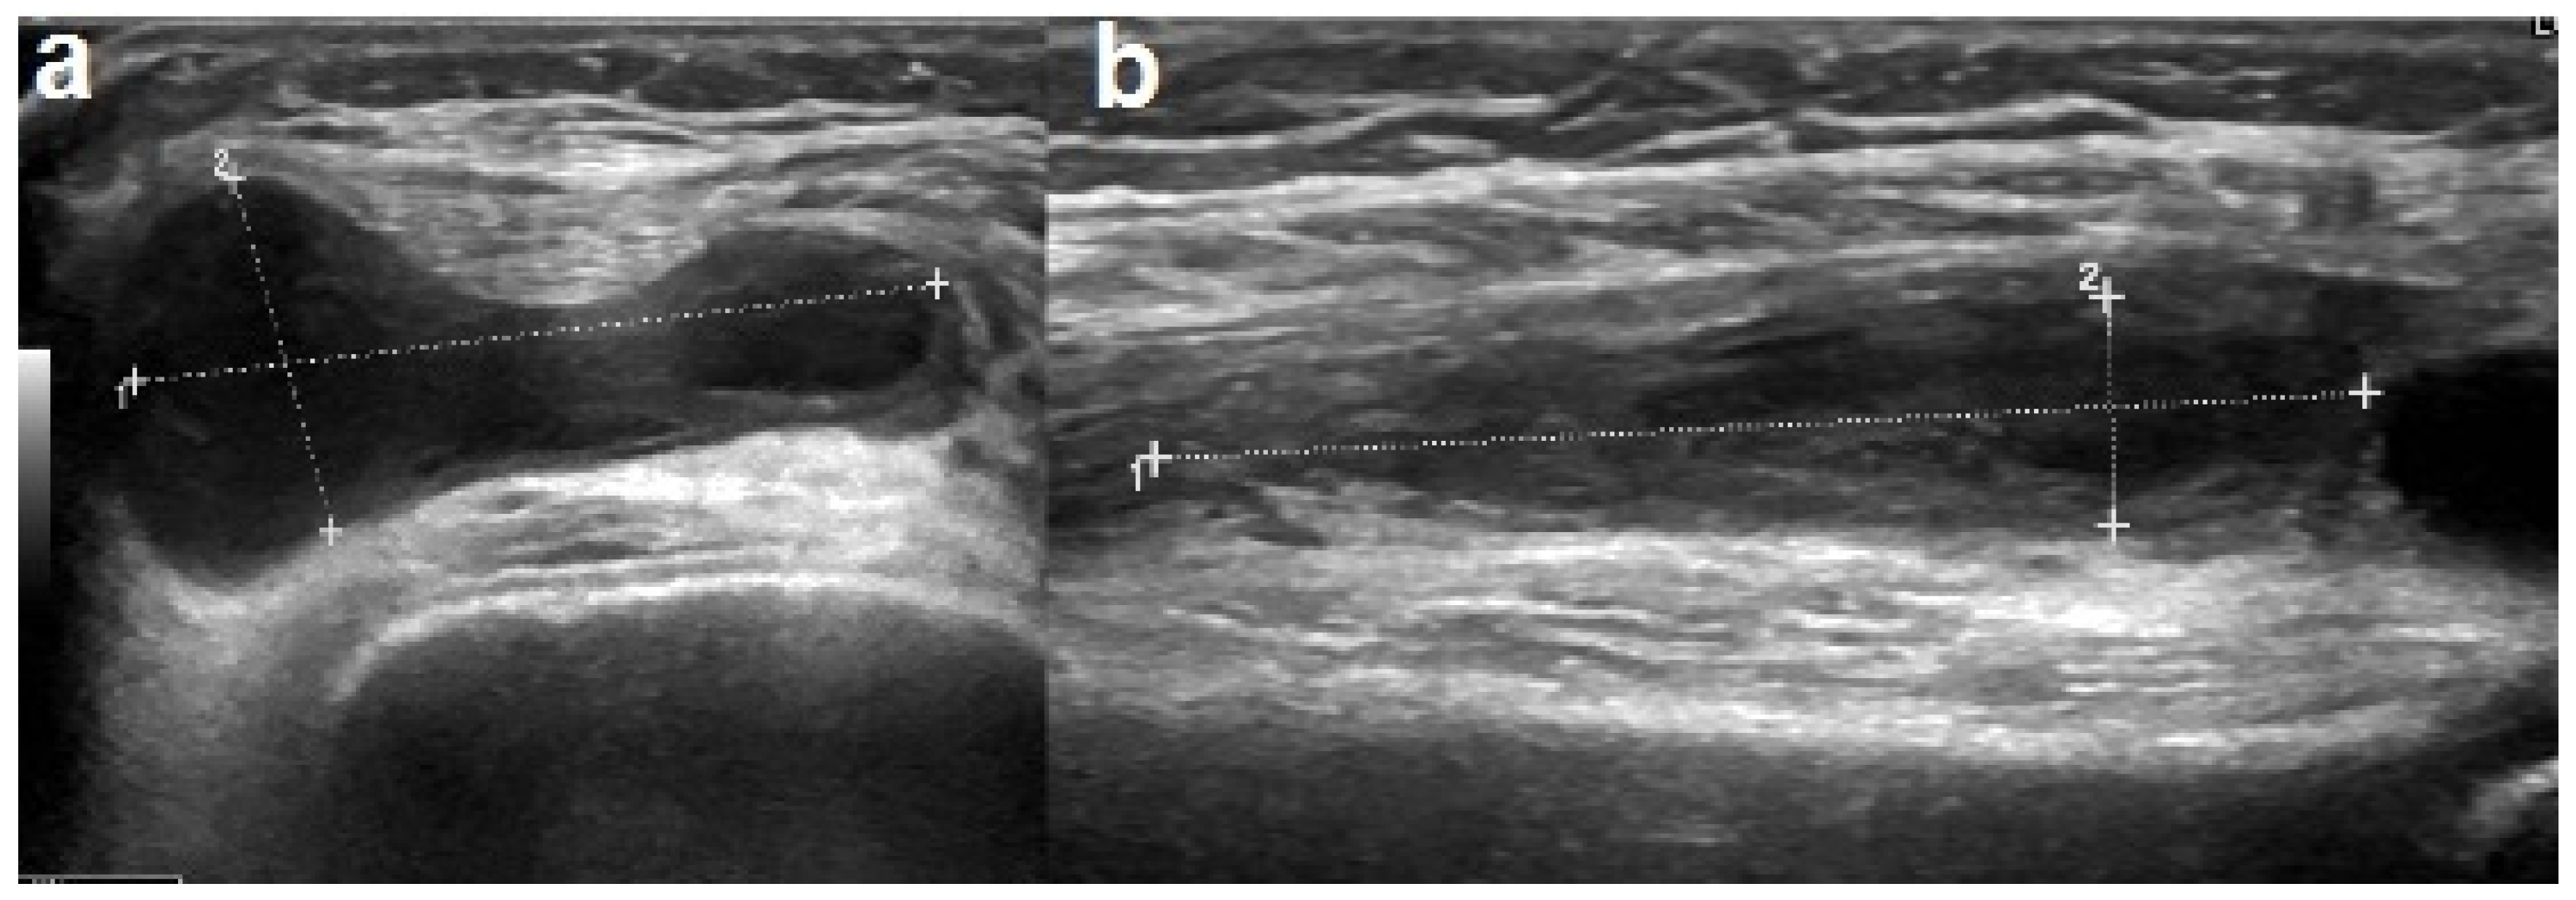

2. Case Report